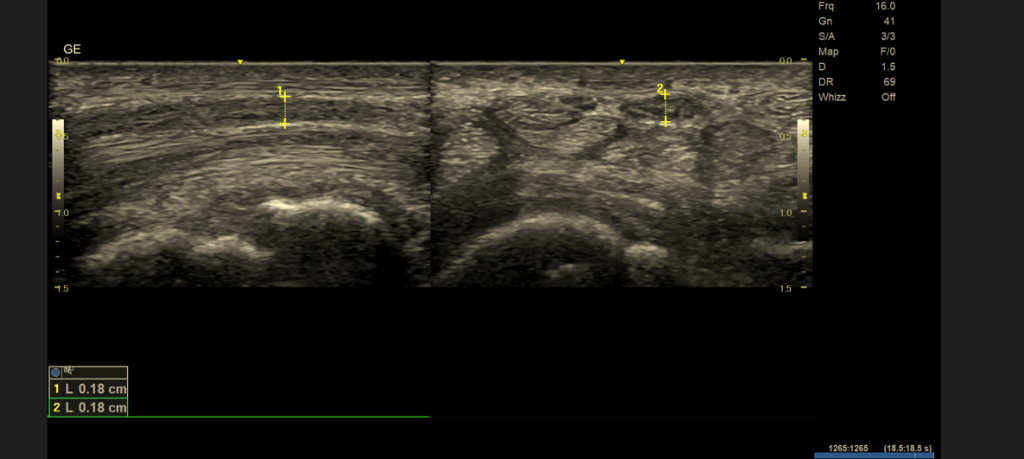

👉 Nerwy cienkie (< 3 mm) – diagnostyka praktycznie wyłącznie za pomocą USG wysokiej rozdzielczości

Nerwy cienkie (< 3 mm) – tylko USG wysokiej rozdzielczości

- rozdzielczość sięgającą 0,1–0,2 mm

- możliwość oceny fascikularnej budowy nerwu

1. Rozdzielczość przestrzenna

- USG: zdecydowanie lepsza w ocenie nerwów cienkich i powierzchownych

2. Możliwość badania dynamicznego

- USG: ocena nerwu w ruchu, podczas zgięcia, ucisku, prowokacji bólu

- MR: badanie statyczne

🔍 Wniosek: zespoły uciskowe i neuropatie dynamiczne → USG

Dlaczego USG jest lepsze od MR w ocenie cienkich nerwów?

USG oferuje znacznie wyższą rozdzielczość przestrzenną niż MR. Dzięki temu możliwa jest:

- ocena struktury pęczkowej nerwu,

- wykrycie pogrubienia, obrzęku lub ucisku,

- dokładna lokalizacja miejsca uszkodzenia.